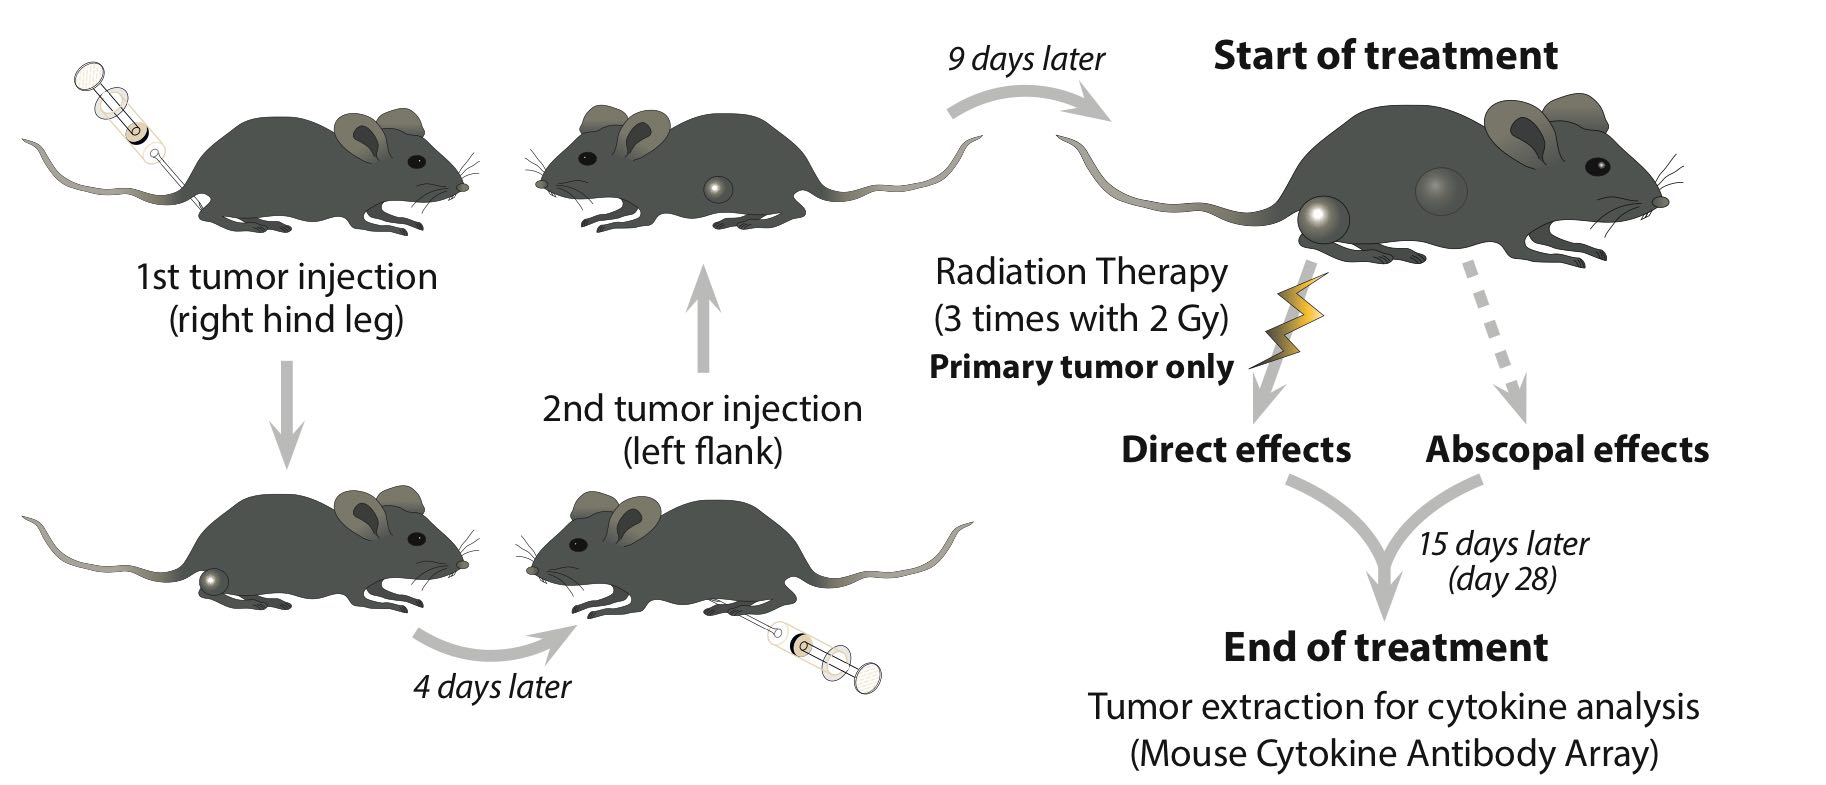

Anecdotal clinical reports suggest that local tumor irradiation alone may also exert systemic or abscopal anti-tumor immune effects with subsequent control of non-irradiated metastases. This study used a syngeneic mouse model with a primary irradiated and a secondary non-irradiated tumor to study abscopal effects of local radiotherapy combined with RNActive® vaccination.